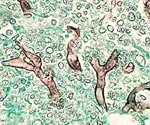

What is Mucormycosis?